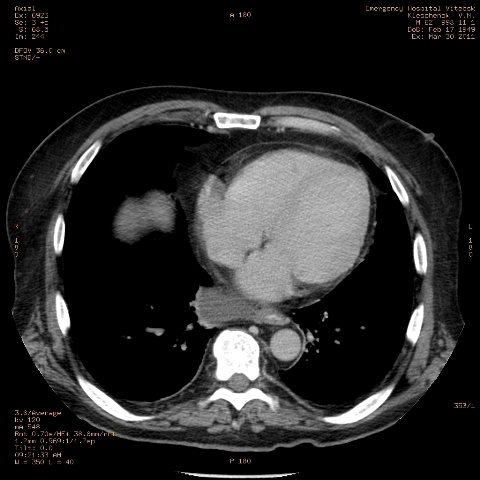

при исследовании органов брюшной полости по поводу абсцесса печени, в нижнем этаже средостения выявлено образование неоднородной плотности (-5-+25), при в/в контрастировании - не контрастируется, при per os - затёков из пищевода нет, неправильно овальной формы. предположительно киста перикарда? спасибо за помощь!

Может быть enteric duplication cyst. Как бы есть грыжа жира hiatal. И что с печенью? Мало срезов.